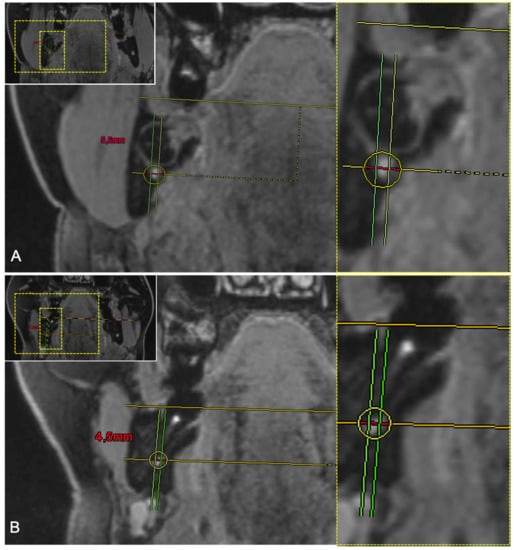

| Second Molar | Axial | Sagittal | Coronal |

|---|---|---|---|

| IAC in CBCT | 4.22 ± 0.78 mm | 3.86 ± 0.9 mm | 5.28 ± 0.83 mm |

| IAC in MRI | 4.23 ± 1.21 mm | 3.09 ± 1.09 mm | 5.62 ± 0.87 mm |

| IAN in MRI | 3.13 ± 0.89 mm | 2.4 ± 0.8 mm | 4.1 ± 0.78 mm |

| Conversion factor IAC (CBCT): IAN (MRI) | 1.692 ± 0.864 | 1.691 ± 0.864 | 1.258 ± 0.407 |

| Conversion factor IAC (MRI): IAN (MRI) | 1.407 ± 0.427 | 1.424± 0.727 | 1.396 ± 0.223 |